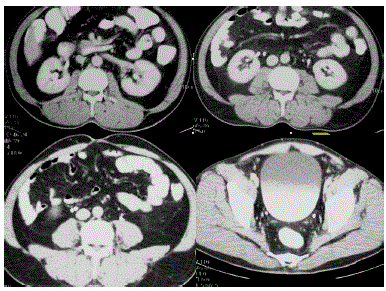

A duplicação ureteropélvica completa pode ser relacionada à regra de Weigert-Meyer.

Correlacionando com a imagem disponibilizada, marque a relação verdadeira.